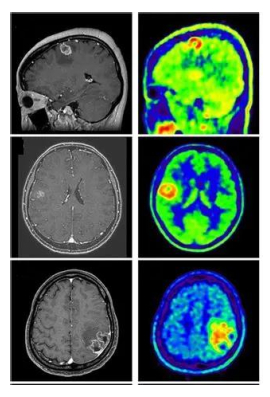

[46] R. Ranjbarzadeh, A. Keles, M. Crane, M. Bendechache, Comparative analysis of real-clinical MRI and BraTS datasets for brain tumor segmentation, CP887, IET, (2024), pp. 39–46.

[48] S. Suchitra, Parkinson disease prediction using deep learning algorithm, rp-9788770040723.217.

[55] R. Ranjbarzadeh, A. Caputo, E. B. Tirkolaee, S. J. Ghoushchi, M. Bendechache, Brain tumor segmentation of MRI images: A comprehensive review on the application of artificial intelligence tools, Comput. Biol. Med., 152 (2023), 106405. https://doi.org/10.1016/j.compbiomed.2022.106405 doi: 10.1016/j.compbiomed.2022.106405

[61] N. T. Sarshar, S. Sadeghi, M. Kamsari, M. Avazpour, S. J. Ghoushchi, R. Ranjbarzadeh, Advancing brain MRI images classification: Integrating VGG16 and ResNet50 with a Multi-verse optimization method, (2024).

[62] R. Ranjbarzadeh, A. B. Kasgari, S. J. Ghoushchi, S. Anari, M. Naseri, M. Bendechache, Brain tumor segmentation based on deep learning and an attention mechanism using MRI multi-modalities brain images, Sci. Rep., 11 (2021), 10930. https://doi.org/10.1038/s41598-021-90428-8 doi: 10.1038/s41598-021-90428-8

[68] A. B. Kasgari, R. Ranjbarzadeh, A. Caputo, S. B. Saadi, M. Bendechache, Brain tumor segmentation based on zernike moments, enhanced ant lion optimization, and convolutional neural network in MRI images, in: Metaheuristics and Optimization in Computer and Electrical Engineering, Hybrid and Improved Algorithms, Springer, 2 (2023), pp. 345–366.

[73] R. Ranjbarzadeh, M. Crane, M. Bendechache, The impact of backbone selection in Yolov8 Models on brain tumor localization, Iran J. Comput. Sci., (2025), 1–23. https://doi.org/10.1007/s42044-025-00258-4 doi: 10.1007/s42044-025-00258-4

[75] R. Ranjbarzadeh, A. Keles, M. Crane, S. Anari, M. Bendechache, Secure and decentralized collaboration in oncology: A blockchain approach to tumor segmentation, IEEE, 2024, pp.1681–1686.